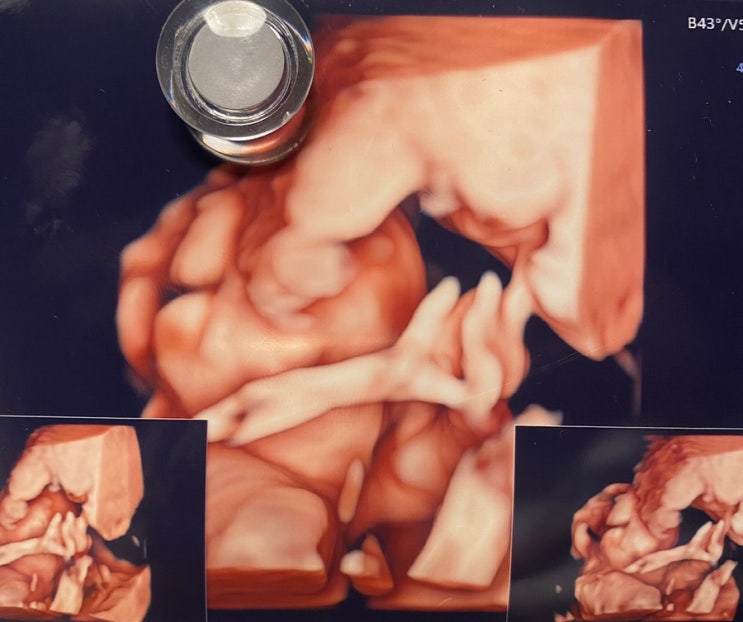

[임신초기 ~16주 기록] 입덧 / 임산부 심부정맥혈전증 / 주수별 초음파 기록 등

평소 놀러다니는 것만 블로그에 포스팅했는데 임신 35주 막달인 지금, 가만히 생각해보니 인생에서 소중한 ...